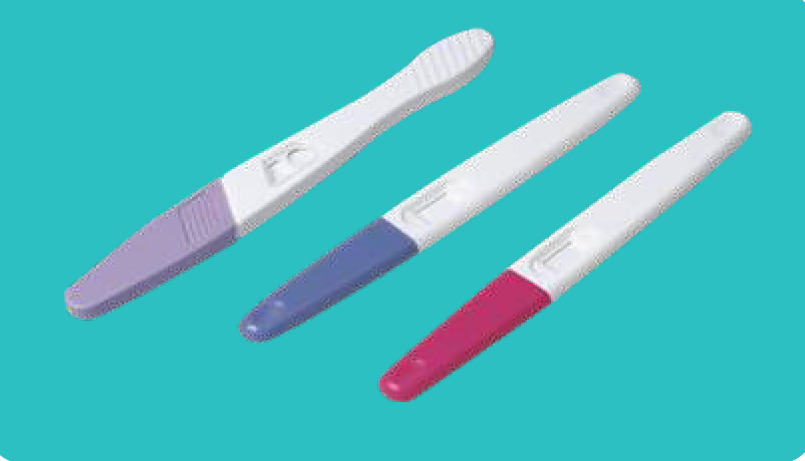

Hcg Test Devise

Size: 3.0mm/3.5mm/4.0mm

Specimen: Urine, Urine/Serum

Sensitivity: 10mIU/ml, 15mlIU/ml, 20mIU/ml, 25mIU/ml

Packing: 2500pcs/ctn 75x44x39cm

Hcg Midstream

Size: 3.0mm/4.0mm/5.5mm/6.0mm/7.0mm

Specimen: Urine, Urine/Serum

Sensitivity: 10mIU/ml, 15mlIU/ml, 20mIU/ml, 25mIU/ml

Packing: 2000pcs/ctn 75x39x44cm

HCG Test Strip

Size: 2.5mm

Packing: 1pc/foil pouch, 50pcs/box, 5000pcs/ctn

Carton Size: 75x29x56cm